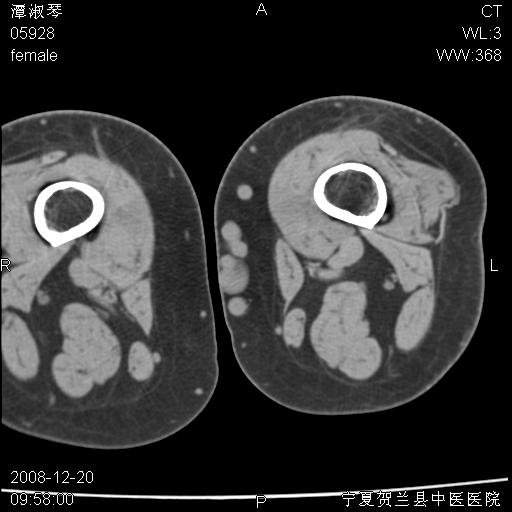

标题: CT17526:请各位看看是啥?

左胫骨下端松质骨及髓腔内可见点片状高密度灶,骨皮质无明显膨胀及变薄。病变范围较长。支持骨梗死,退行性骨关节病,膝关节积液

支持骨梗死,退行性骨关节病,膝关节积液.

左股骨下段骨梗死。双膝退变。